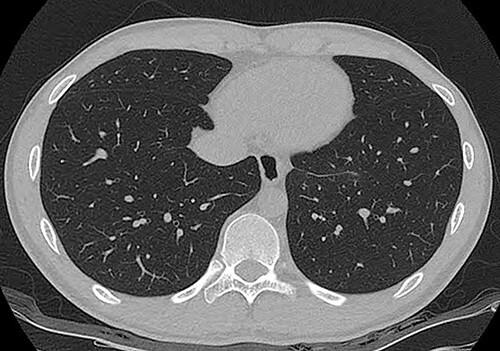

Esophageal bronchogenic cysts are very rare. A bronchogenic cyst is a congenital malformation resulting from abnormal sprouting of primitive bronchi because of a foregut bronchopulmonary malformation. An 18-year-old patient with a cystic tumor in the left posterior mediastinum was identified. The mediastinal tumor was removed by uniportal video-assisted thoracoscopic surgery. The operation was performed in the prone position through a single 4-cm incision on the lateral scapular line in the left ninth intercostal space. After tumor resection, the dissected esophageal muscle and mediastinal pleura were sutured with two continuous barbed sutures. The operation took 80 min. A biopsy confirmed the diagnosis of esophageal bronchial cyst. Diet was started on the evening of the operation. The chest tube was removed on the 1st postoperative day, and the patient was discharged without any problems on the 2nd postoperative day.

食管支气管囊肿非常罕见。支气管囊肿是一种先天性畸形,由于前肠支气管肺畸形导致原始支气管异常发芽所致。一名18岁的患者被发现左后纵隔有一个囊性肿瘤。通过单孔电视辅助胸腔镜手术切除纵隔肿瘤。手术在俯卧位进行,通过左侧第九肋间肩胛下线处一个4厘米的单一切口。肿瘤切除后,用两根连续倒刺缝线缝合切开的食管肌层和纵隔胸膜。手术耗时80分钟。活检确诊为食管支气管囊肿。术后当晚开始进食。术后第1天拔除胸管,患者术后第2天顺利出院。